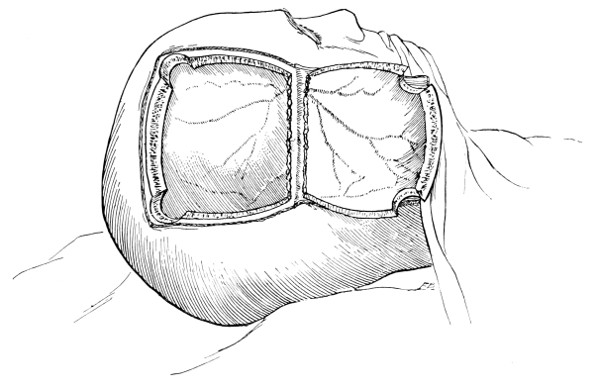

Fig. 17. First Stage in the Formation of an Osteoplastic Flap. Gigli’s saw, protected from the dura mater by the special director, passing between the two trephine-holes. For further description, see text.

[27]

Fig. 18. Second Stage in the Formation of an Osteoplastic Flap. The bone-flap turned down and the dura mater exposed.

Fig. 19. Third Stage in the Formation of an Osteoplastic Flap. The dural flap turned down and the brain exposed. Note the relation of the scalp, bone, and dural incisions to one another.